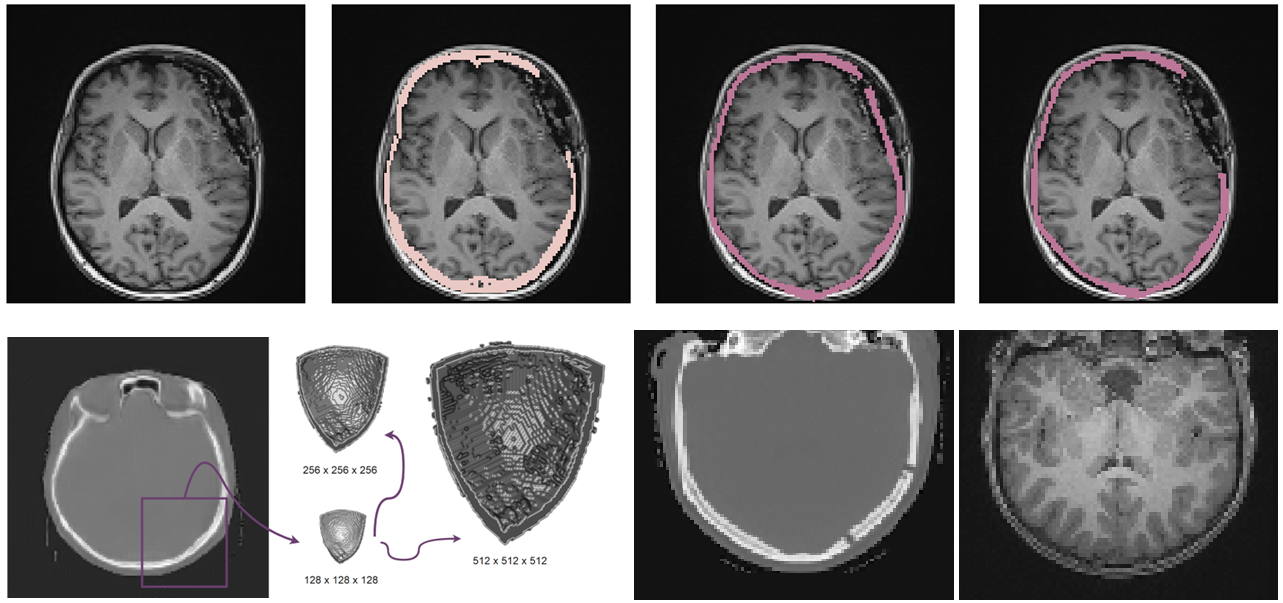

Refer to caption

Figure 1: Inference with the use of the proposed solution. Firstly, the generator from the CUT framework is applied. This is followed by a super-resolution module. Next, we perform histogram matching using a different CT sample from the dataset, which does not need to be correlated with the input MR image. After this, Hounsfield thresholding is applied, followed by binary operations, to achieve the final skull segmentation results. The entire process leverages synthetic CT for skull segmentation via MR-to-CT modality translation.

Figure 2: The overview of the pipeline for the Contrastive Unpaired Translation and Laplacian Pyramid Super-Resolution Network. Note that we work on 3-D tensors, the 2-D representations are used only for visualization simplicity.

Figure 3: Sampling procedure for patchwise contrastive estimation of real MR \leftrightarrow synthetic CT, and real CT \leftrightarrow identity CT. We show a 2-D view for better visualization.

Figure 5: Top: Results of translation and segmentation on defected skulls (from left to right: input MR, matched CT mask, synthetic CT mask, synthetic CT mask with removed implant area). Bottom left: Super-resolution of synthetic skull. Bottom right: MR-to-CT translation on child’s skull.